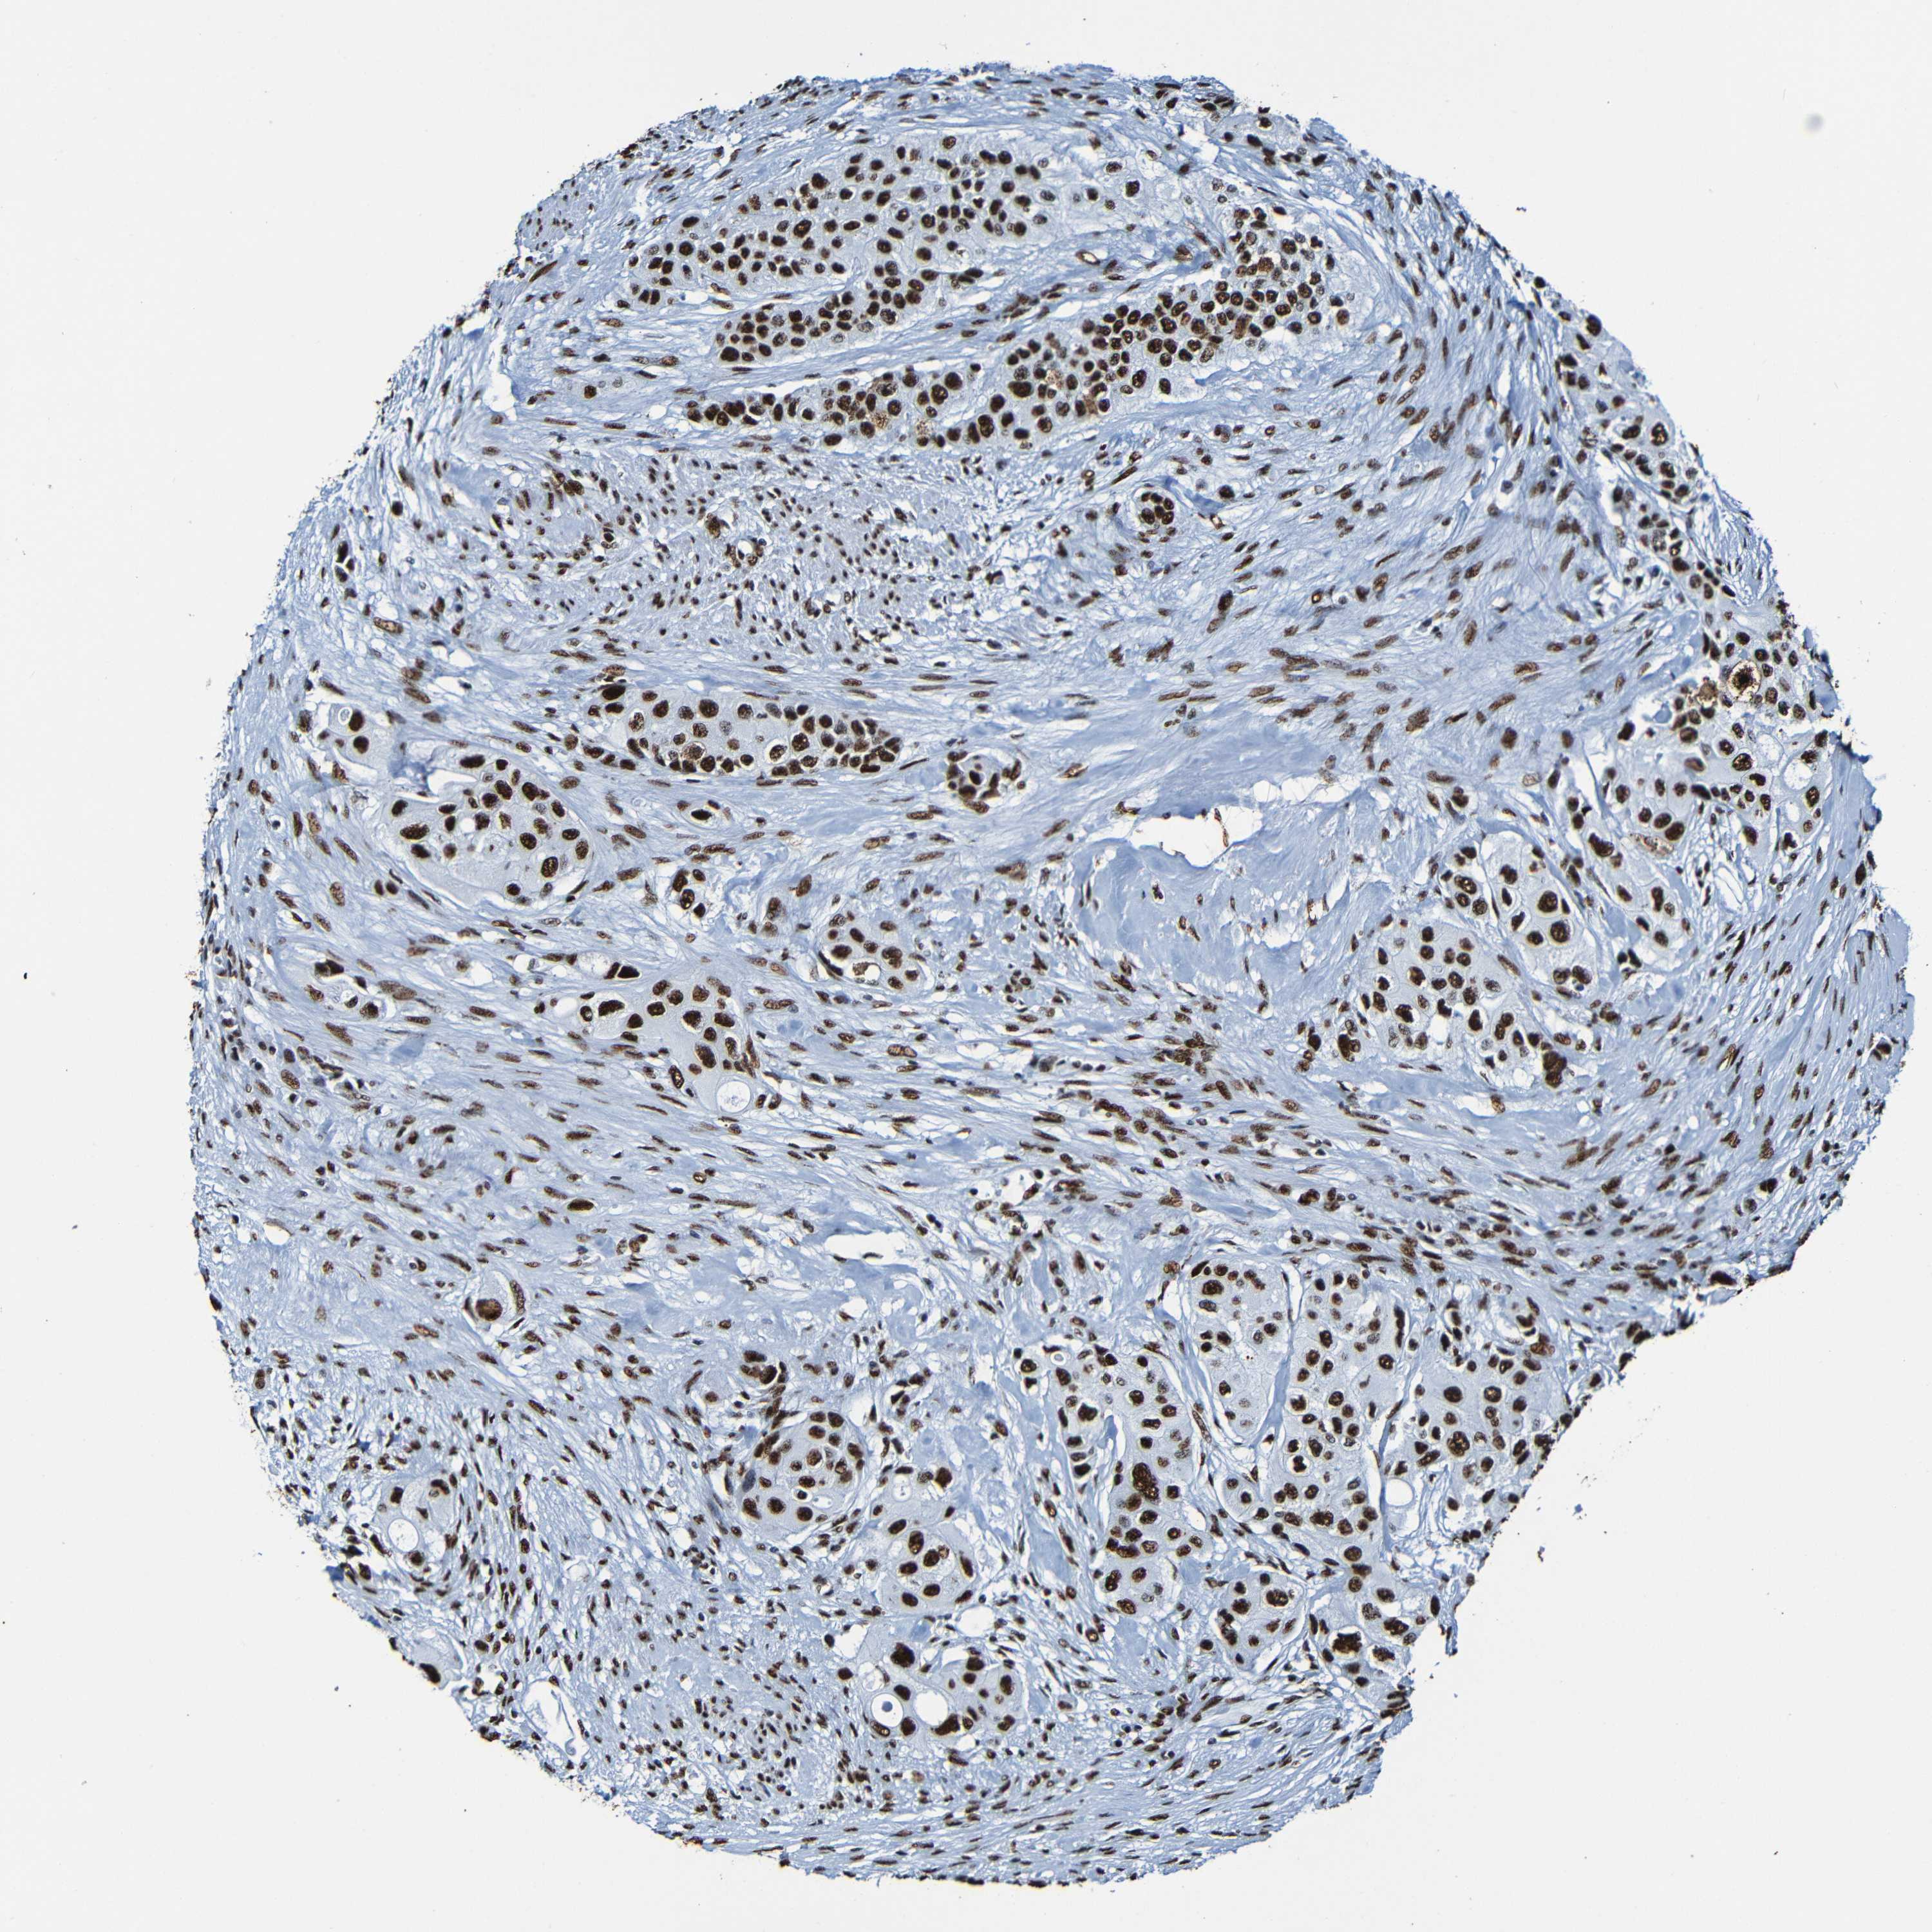

UROTHELIAL CANCER - Protein expressioni

A mouse-over function shows sample information and annotation data. Click on an image to view it in a full screen mode. Samples can be filtered based on level of antibody staining by selecting one or several of the following categories: high, medium, low and not detected. The assay and annotation is described here.

Antibody stainingi

Antibody staining in the annotated cell types in the current human tissue is reported as not detected, low, medium, or high, based on conventional immunohistochemistry profiling in selected tissues. This score is based on the combination of the staining intensity and fraction of stained cells.

Each image is clickable and will lead to virtual microscopy that enables deeper exploration of all samples and also displays staining intensity scores, fraction scores and subcellular localization as well as patient and tissue information for each sample.

Antibody HPA056981

Antibody CAB012986

Staining

High

Medium

Low

Not detected

Intensity

Strong

Moderate

Weak

Negative

Quantity

>75%

75%-25%

<25%

None

Location

Nuclear

Cytoplasmic/membranous

Cytoplasmic/membranous,nuclear

Urothelial carcinoma, Low grade